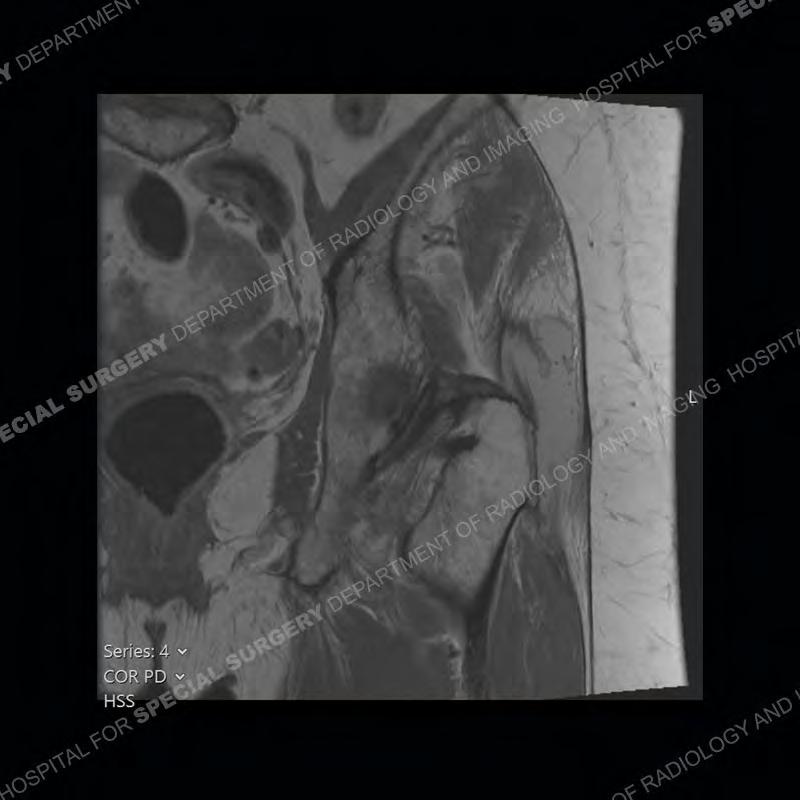

The radiograph is not particularly contributory in this case. The MRI demonstrates markedly abnormal architecture of the gluteus minimus and anterolateral band of the gluteus medius. Portions of the tendons are high signal, portions are highly attenuated, and portions are disrupted. A large, complex fluid collection is present in the adjacent soft tissue.

Diagnosis: Gluteal Tendinosis and Disruption with Complex Trochanteric Bursal Collection

Not as much of a diagnostic dilemma as many of the other cases shown but just a nice example of the pathology seen of the gluteal tendons and a cause of trochanteric pain. Although, frequently thought of in isolation, trochanteric bursitis or bursal thickening is much more commonly a reactive change to underlying pathology of the subjacent gluteal tendons. The gluteus medius is divided into a posterior band and an anterolateral band. Tendinosis and partial tearing very commonly will involve the gluteus minimus and especially the more posterior fibers and then propagate into the anterior lateral band of the gluteus medius. Involvement of the posterior band of the medius is much less common and engenders a marked degree of functional impairment.

The bursae about the greater trochanter can be a little bit confusing especially given the terminology. Trochanteric bursitis is implied to mean the subgluteus maximus bursa which is present deep to the maximus and just lateral/superficial to the trochanter. That is the bursa involved in this case. In this case the complexity of the bursa relates to the tendon tearing with inflammatory change and probably hemorrhage accounting for the complexity. Two other, less frequently involved bursa are also present. The subgluteus medius and subgluteus minimus bursa are found just deep to the named tendons. Although pathology does frequently follow the previously described pattern it is possible to have isolated pathology to either the medius or minimus.